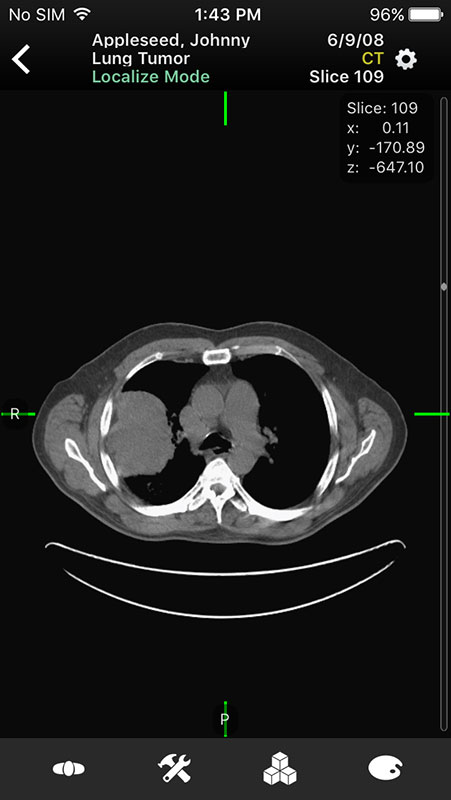

These sample images feature same imaginary patients and cases from the Mobile MIM app and contain X-ray, PETCT, MR, and ultrasound scans, alongside the name of the procedure.

Tapping on the image would initiate the download, which may vary in size, from 2MB to 76.5MB. After the download is completed, the image would open, and if the image is part of the series, you'd be able to view the first image until the whole series is downloaded.

Just like in Mobile MIM app, images open in multi-planar view allowing users to choose series depending on the type of imaging technique, add annotation, or measure the image.